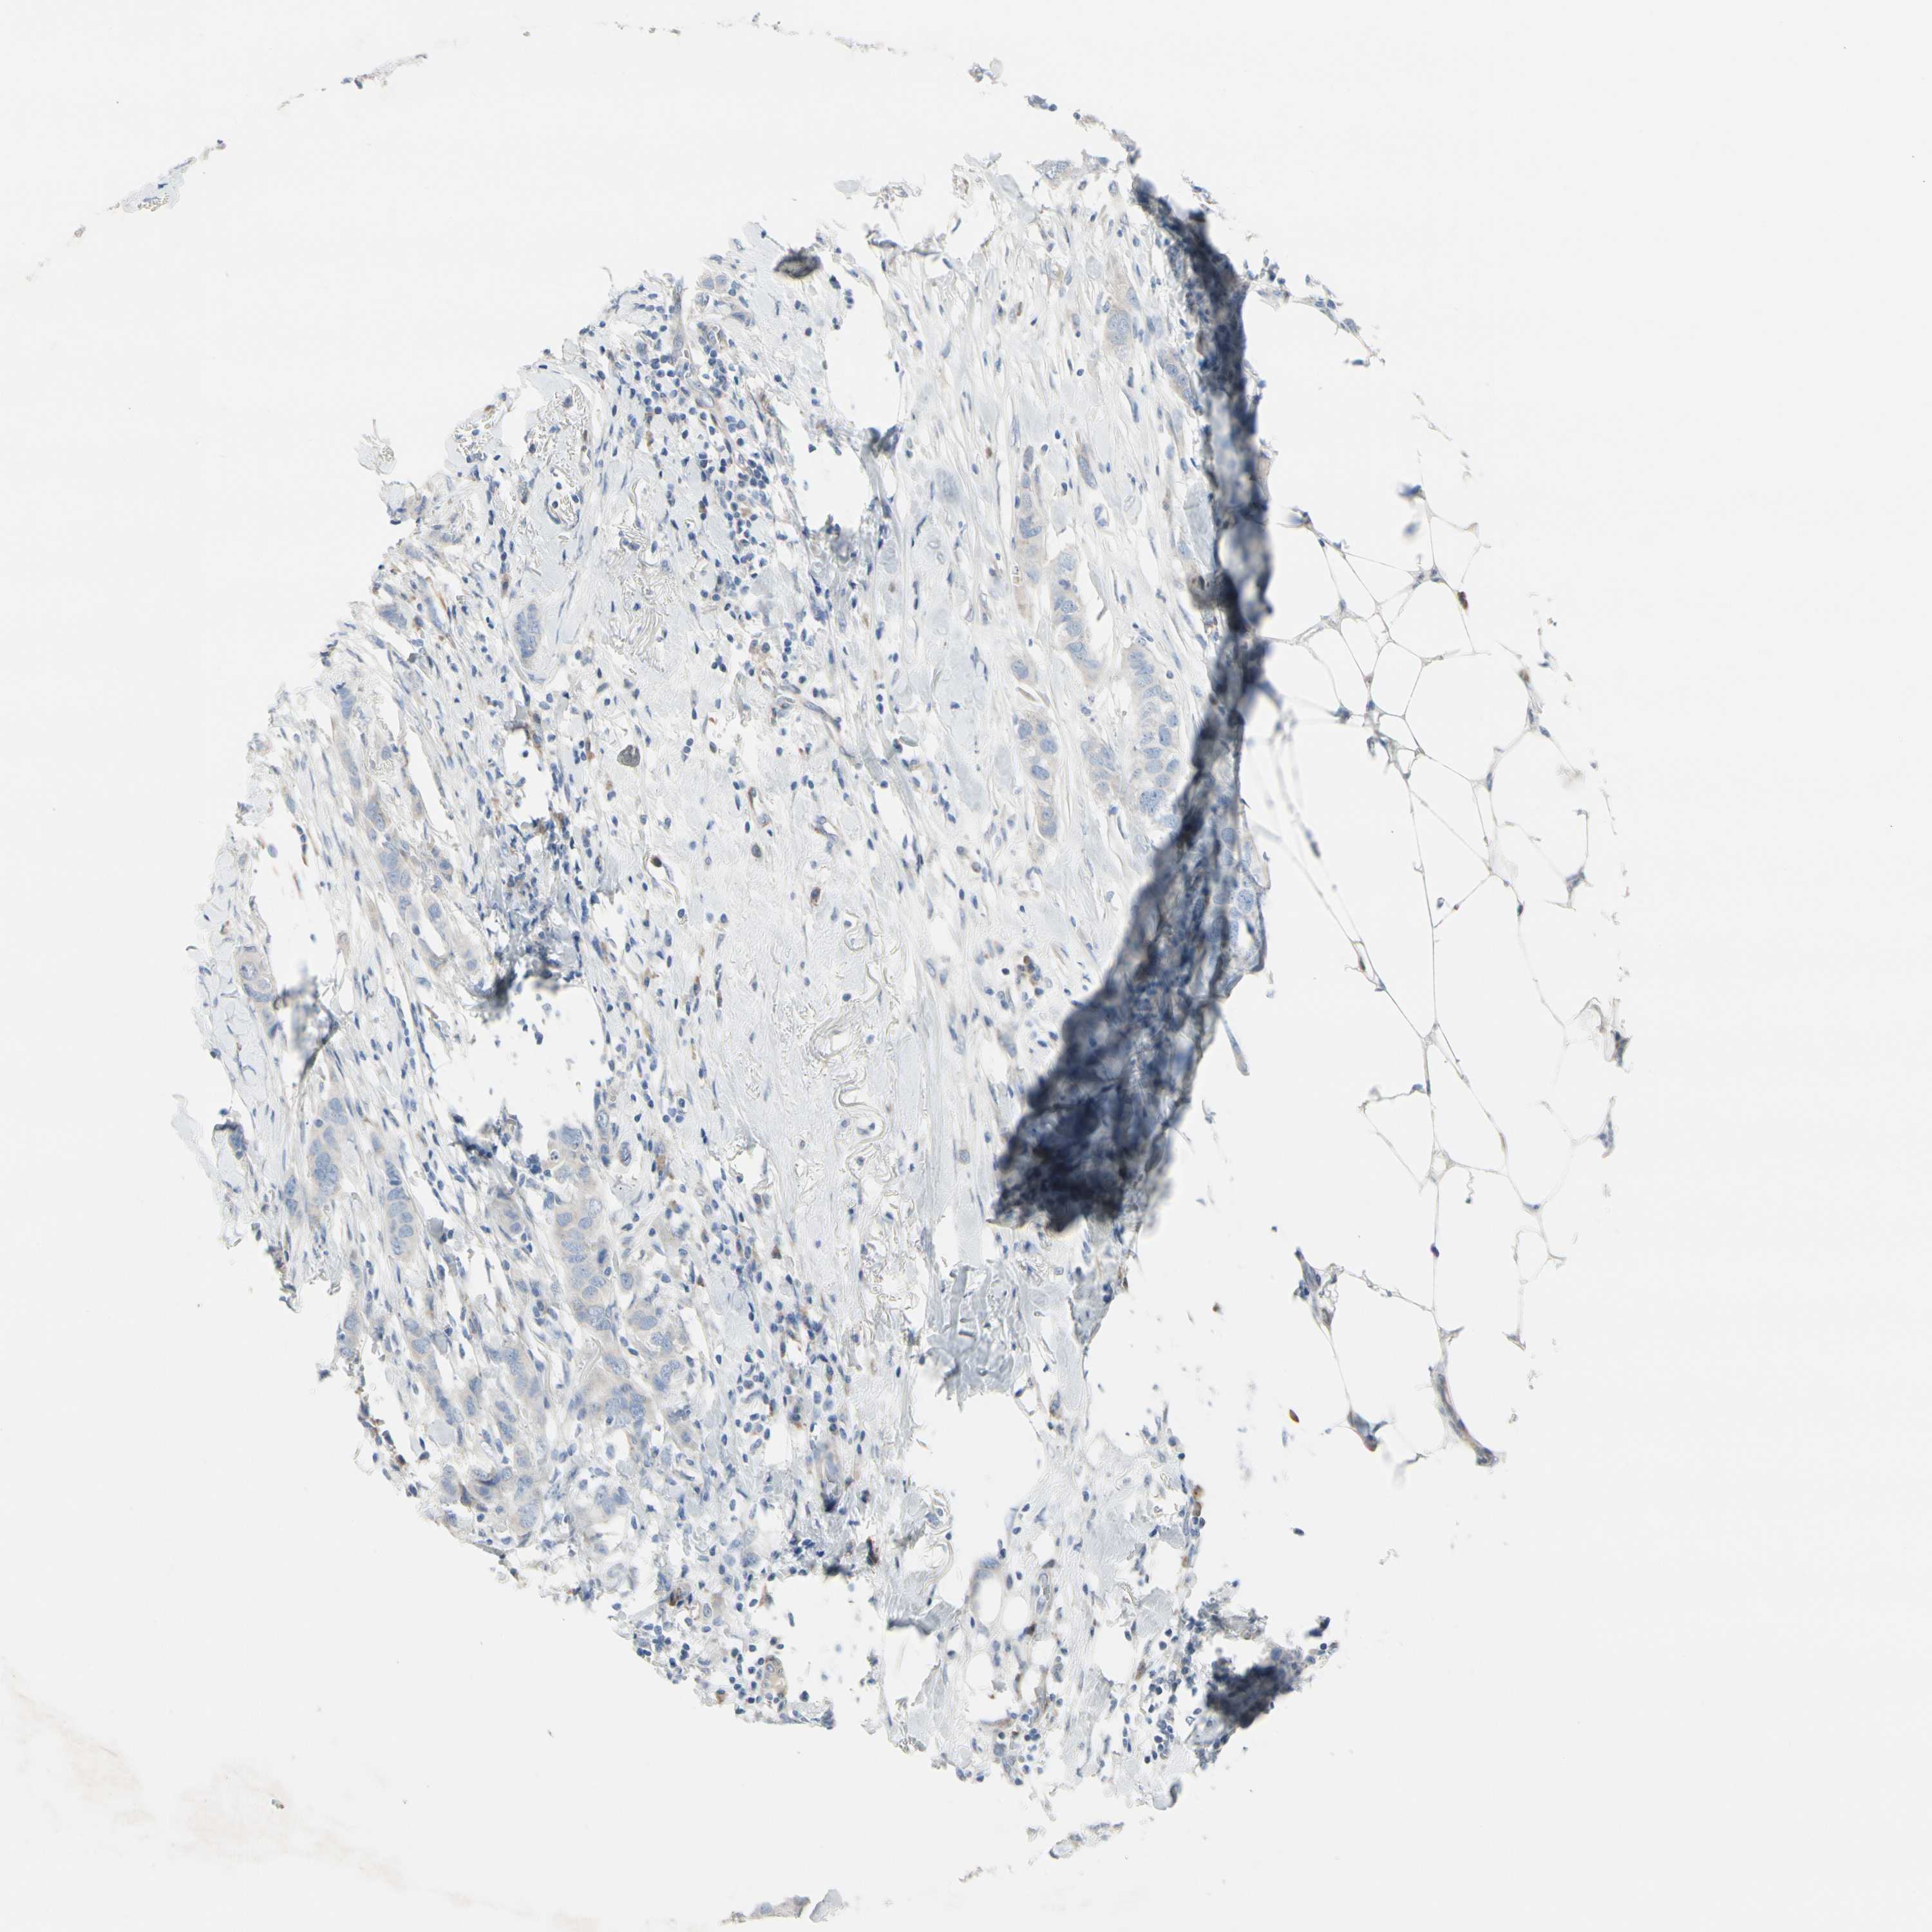

CANCER BREAST CANCER Show tissue menu

BRCA TCGA BRCA VALIDATION PROTEIN EXPRESSION

Breast cancer

Human cancer